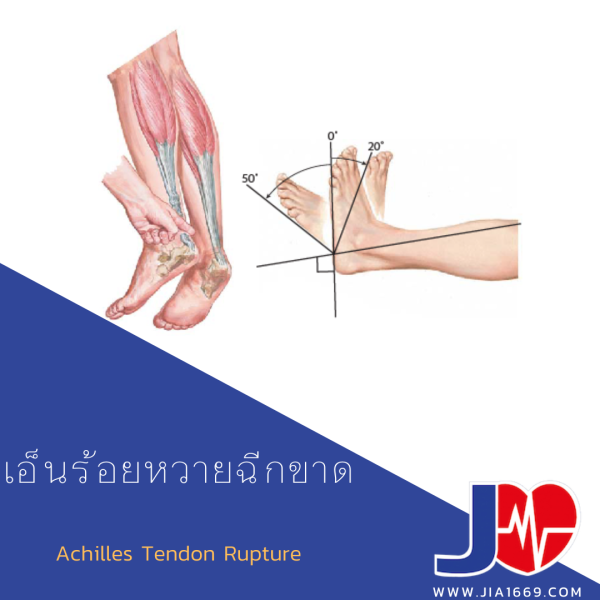

เอ็นร้อยหวายอักเสบ จุดเกาะเอ็นอักเสบ มีอาการตึง เจ็บ คลำได้กระดูกงอก เอ็นร้อยหวายขาด อาการ การรักษา การผ่าตัด พักฟืนกี่เดือนหาย

เอ็นร้อยหวายขาด อาการ การรักษา การผ่าตัด พักฟืนกี่เดือนหาย เอ็นร้อยหวายยืดกล้ามเนื้อขาของมนุษย์เท้ากล้ามเนื้อ Latissimus หลัง, แขน …

เอ็นร้อยหวายขาด ชีวิตลำบากแน่!! เช็คอาการดูก่อนปัญหาลุกลาม – jkgroup168 เอ็นร้อยหวายอักเสบ – (Achilles Tendinitis)

เอ็นร้อยหวายอักเสบ – (Achilles Tendinitis) ดาวน์โหลดฟรี | เอ็นร้อยหวายแตกอื่น ๆ, ร้อยหวาย, Achilles Tendon png …

เอ็นร้อยหวายฉีกขาด ในปี 2023 | สุขภาพ, ความรู้, กรอบ Hamstring แปลว่า เอ็นร้อยหวาย | Eng Hero เรียนภาษาอังกฤษ ออนไลน์ ฟรี

เอ็นร้อยหวายฉีกขาด – jia1669 ท่าบริหารเอ็นร้อยหวาย แก้เอ็นร้อยหวายตึง เอ็นร้อยหวายอักเสบ เอ็นร้อยหวายบวม